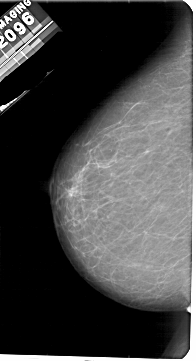

A_1871_1.RIGHT_MLO

LEFT_MLO LINES 5491 PIXELS_PER_LINE 3211 BITS_PER_PIXEL 12 RESOLUTION 43.5 NON_OVERLAY